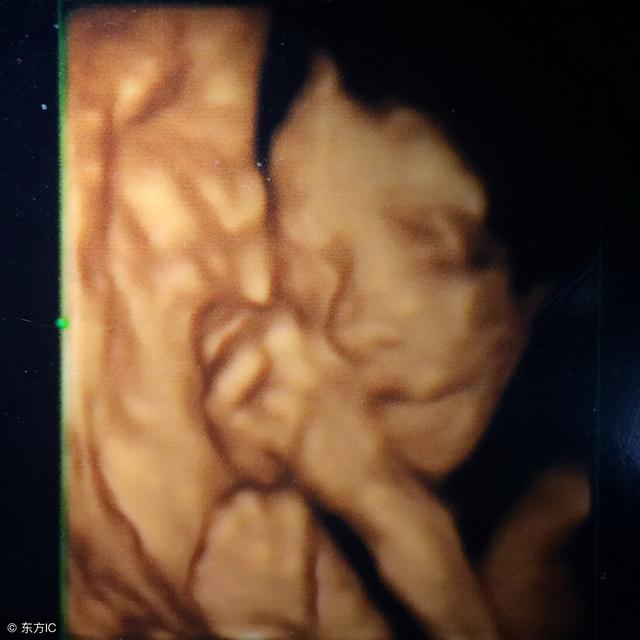

怀孕对每个女人来说 , 都算得上是人生大事 。 而各类产检则是每个孕妈妈在孕期必须要做的 。 在所有产检中 , 四维彩超则是孕期最重要的产检项目之一 , 也被称为“宝宝人生第一张照片” 。

可是 , 不少孕妈妈在做这项产检的过程中 , 总会出现宝宝不配合的情况 。 比如小宝贝捂着脸或是挡着某个部位就是不让看 , 或者出现胎儿左手或右手一直不动的情况 。 就跟网友青青所说的一样 , 她在做四维彩超检查时宝宝就不配合 , 彩超显示胎儿左手一直不动 , 这就让检查受阻了 。

记得表妹在怀孕期间 , 她的每次产检都不会落下 。 但她在做四维彩超的时候 , 也是出现宝宝压着右手不动的情况 , 医生用力推都推不过来 。 后来就因为这个宝宝不配合 , 我表妹没少跑医院 。 来来回回跑了五次 , 四维彩超才成功 。 好在宝宝右手发育特别正常 , 这才让表妹悬着的心落了下来!